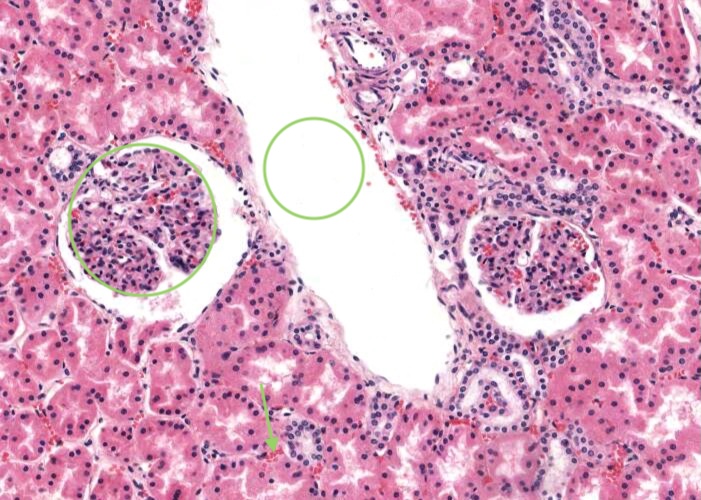

A renal corpuscle is located in the cortex and is the specialised structure where filtration occurs. Each is an aggregation of capillaries enclosed within a cup-shaped capsule called the glomerular (Bowman’s) capsule. Identify red blood cells within these capillaries. The capsule has an outer (parietal) surface layer of squamous epithelial cells and the inner (visceral) layer invests the glomerular capillaries.

The space between the glomerular capillaries and the parietal layer of Bowman’s capsule is referred to as the capsular or urinary space. This space receives plasma fluid that filters through the glomerular capillaries and the visceral layer of epithelial cells called podocytes.

In this H&E section, podocytes are difficult to distinguish from other populations of cells present (e.g. mesangial cells) but assume if you identify a cell nucleus on the periphery of the glomerulus that is larger and more spherical then it is probably a podocyte rather than a flattened nucleus belonging to an endothelial cell. You will see this distinction better when you view the renal corpscule where the basement membrane has been specifically stained and podocytes are definitely outside surface of the basement membrane of the capillary wall.

Interlobular arteries give off tiny afferent arterioles which run into the lobule to supply each renal corpuscle. An afferent arteriole enters a renal corpuscle, breaks up into a tuft of capillaries called a glomerulus, and then collects back into an efferent arteriole instead of a vein. This occurs at the "vascular pole". This is a nice image because it also shows part of a glomerulus with the urinary (tubular) pole visible (see more details in the next item). You may see an arteriole, but it will be impossible to tell whether it is afferent or efferent (although there is a slight hint that it is an afferent arteriole because it is adjacent to a distal convoluted tubule - ignore this though for now!). The efferent arteriole runs for only a short distance before breaking up into a second bed of peritubular capillaries, which nourish the proximal and distal tubules and absorb fluid. Even when these capillaries are collapsed you can easily see abundant red blood cells within their lumens between the convoluted tubules.

Tiny peritubular capillaries (you can see red blood cells within their lumens) are a continuation of the efferent arteriole exiting the glomerulus in the upper and middle cortex and are associated with tubules within the cortical labyrinth. Peritubular capillaries empty into an interlobular vein. In contrast, efferent arterioles exiting juxtamedullary glomeruli gives rise to vasa recta in the medulla.